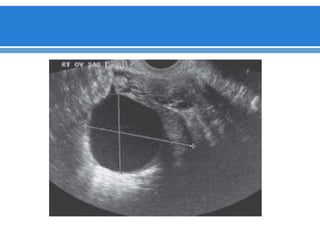

 Posición

 Forma: elíptica, eje cráneo-caudal paralelo a los vasos ilíacos internos

(posterior).

 Eco patrón homogéneo, con medula central mas ecógena.

 Tamaño: el volumen ovárico es el mejor método para determinar su

tamaño.

( Longitud x alto x espesor x 0,5)

•Generalmente lateral o posterolateral al útero en AVF.

•Cuando se sitúa el útero en línea media se encuentra

superior al fondo uterino.

•En RVF se encuentran lateral y superior al útero.